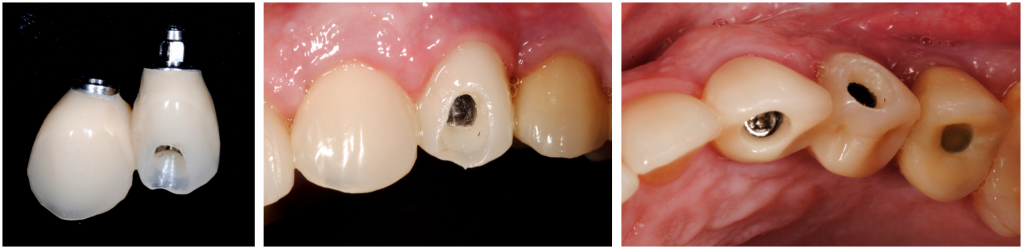

Implant bed preparation at the palatal wall of the socket was performed, and a root-form implant (Klockner ®KL (4,2x12mm)) was placed according to the manufacturer's recommendations without contact with the shield.

The apicocoronal position of the implant platform was 1mm apical to the palatal marginal gingiva. The gap between the shield and implant surface was left to enable blood clot formation.

The final torque was 50nm, and we opted to do immediate non-functional loading through the splinting of provisional to the implant of teeth 24.

Eight months later, the provisional was substituted for a traditional zirconium crown, showing an amazing gingival architecture, which was seen as unchangeable after a 6th, 18th, and 24th month follow-up period.